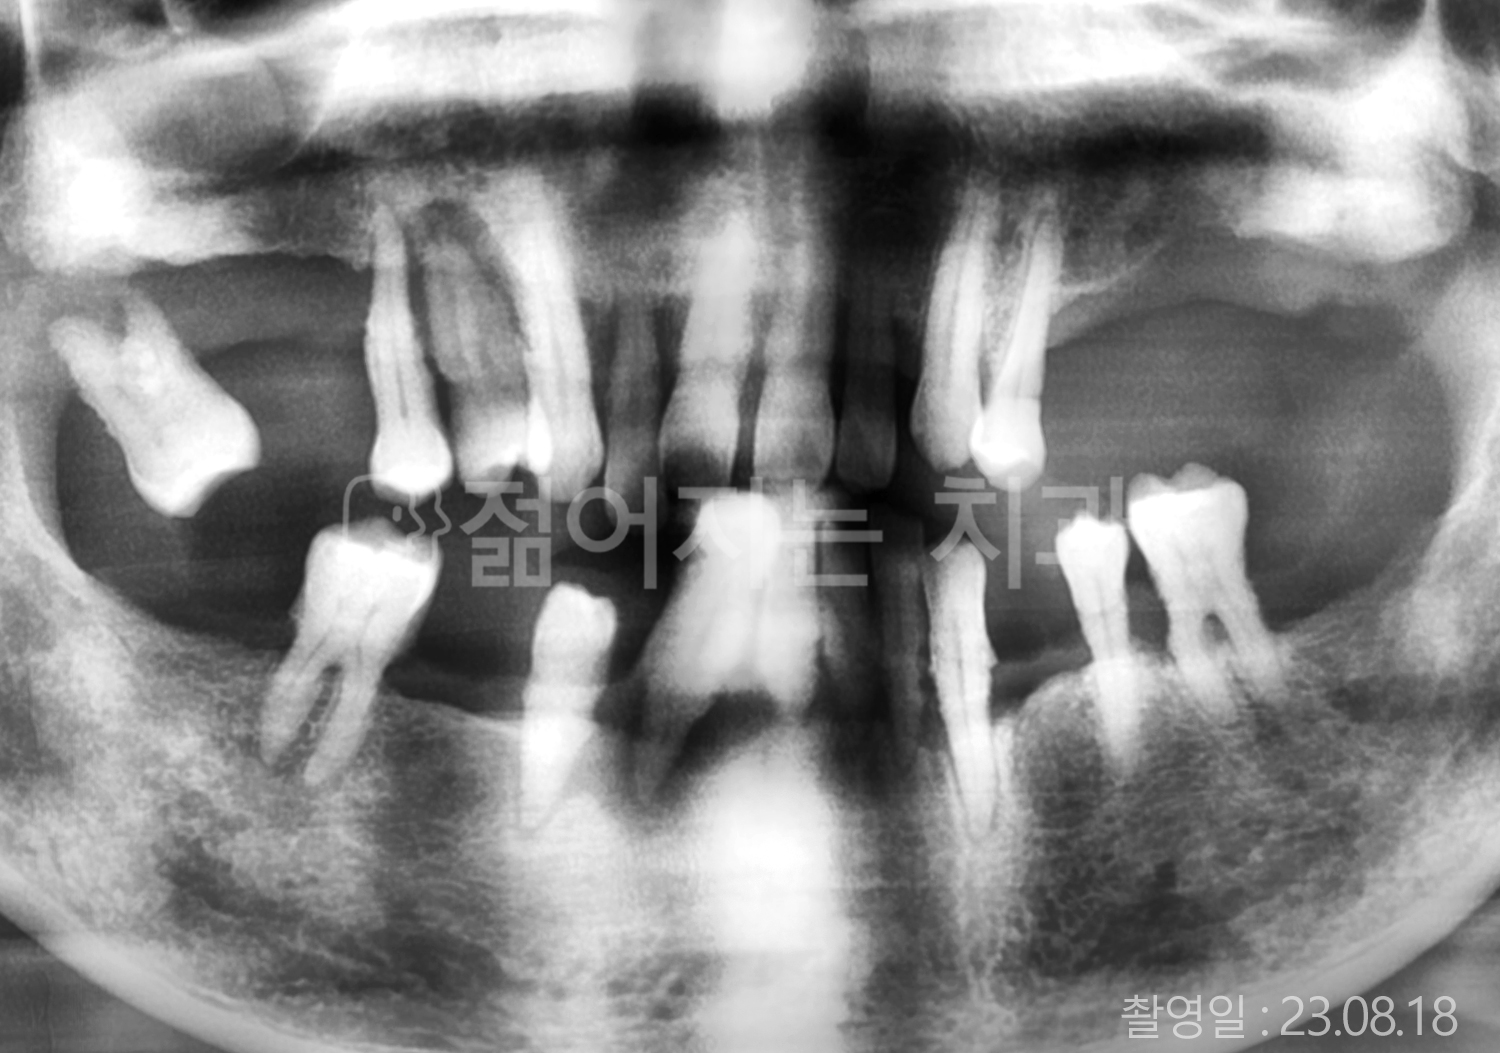

• 60대 전체치아 10개 이상 임플란트